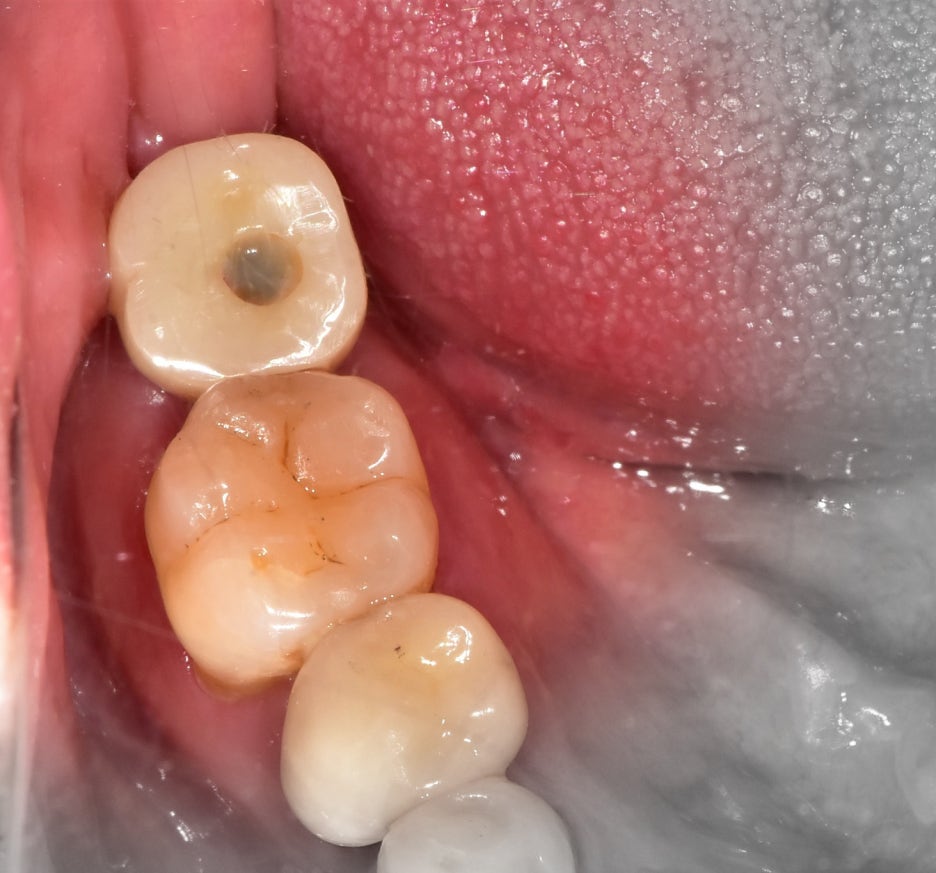

먼저 급한대로, 사랑니 발치를 먼저 진행했습니다. 그리고 나서 왜 임프란트 를 할 수 밖에

없는지 설명을 드렸습니다. 해당 구강 내 사진을 보여드리면서 이미 제 2대구치의 상태를

말씀드렸습니다.